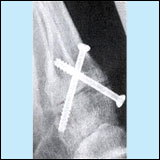

Basisosteotomien

- Korrektur an der Basis des Mittelfußknochens,

keilförmiger Durchtrennung des Knochens und Stabilisierung

mit spezieller Platzhalterplatte

(open-wedge) oder Verkürzung und Keilentnahme

an der Innenseite.

- Vorteil: Korrektur auch größerer

Fehlstellungen,

auch als Reserveeingriff bei erneutem Auftreten

einer Fehlstellung